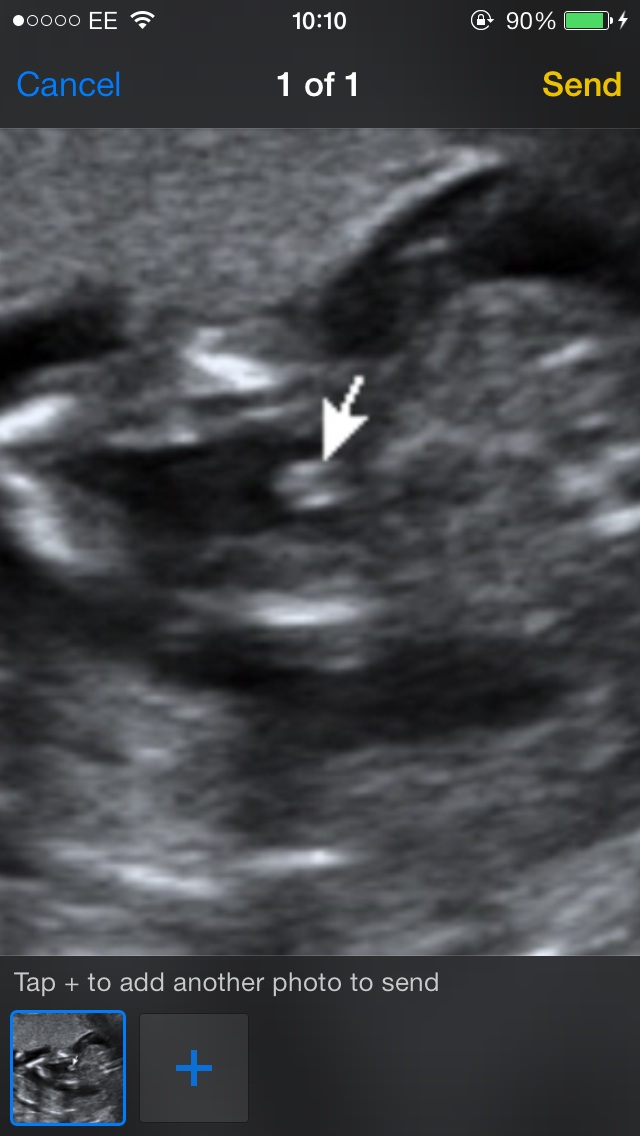

I am asking this for my family member (I am also pregnant, 27w5d with a girl!). At 16 weeks we got a pretty confident prediction of boy (this is the picture that says "its a boy"). Today at the 20 week scan the tech was unsure and said she thought it was a girl. We are now very confused. The other two pictures are from the 20 week scan today. Please help!